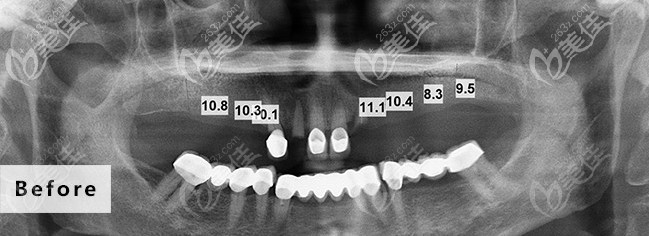

术前照片:

不检查不知道,自己由于牙齿缺失多年,牙槽骨或多或少都有些萎缩了,不能做即刻负重种植,要做传统的点种,我也不懂,就听医生的推荐,选择了性价比比较高的德国种植体。

种植过程好像也蛮快的,我就记得我进去后打了个麻药,医生拿个小钻头一样的东西在嘴里一直动,没多久就好了,也不疼不痒的,据医生说我这个一共植入了7颗植体,还给我看了植体植入后的图片,我也看不懂,植入植体后戴上临时牙冠,似乎跟真牙一模一样,三个月后等待植体稳定后就可以更换牙冠后就能吃饭用了。